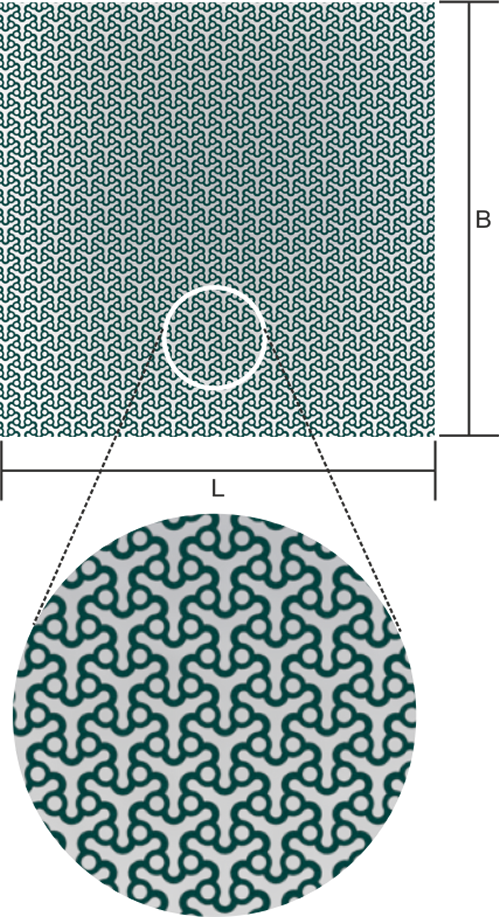

PSI process

Data acquisition

First of all, the necessary data of the patient is gathered with the imaging procedure like computer tomography and afterward stored, e.g. in DICOM- format.

Data transfer

The Data can be saved to CD-ROM, DVD USB flash drive can be send to us. Also you are welcomed to send us the data quickly with our mail id : psi@jayon.in

Data preparation

The data of the patient is prepared and converted by us; a virtual 3D-patient model is created.

Material selection and manufacturing

The material is selected, according to medical and technical aspects; manufacturing is carried out in our modern fabrication centere.